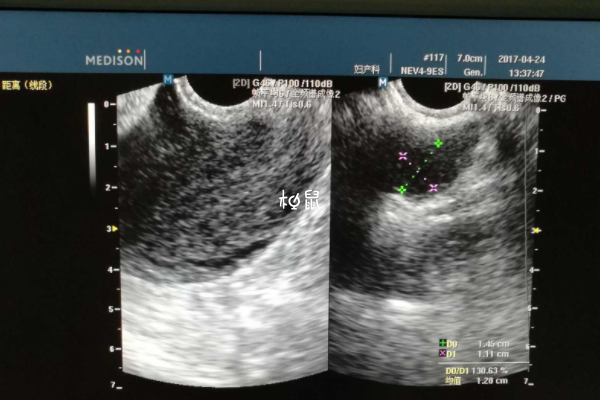

監測卵泡報告想要看卵泡多大了,可以觀察報告單上的數字,比如說報告單上提示18*18mm,就說明有一個卵泡已經長到18mm了,此時卵泡已經發育成熟,有排卵的可能性,回去後安排同房即可。

通過報告單上的數字就能瞭解到卵泡發育情況,有的也會在數字後面對卵泡發育情況做一個解讀,如果不知道卵泡發育多大,可以詢問醫生,在檢查後醫生也會分析結果,有不懂得也可以問。